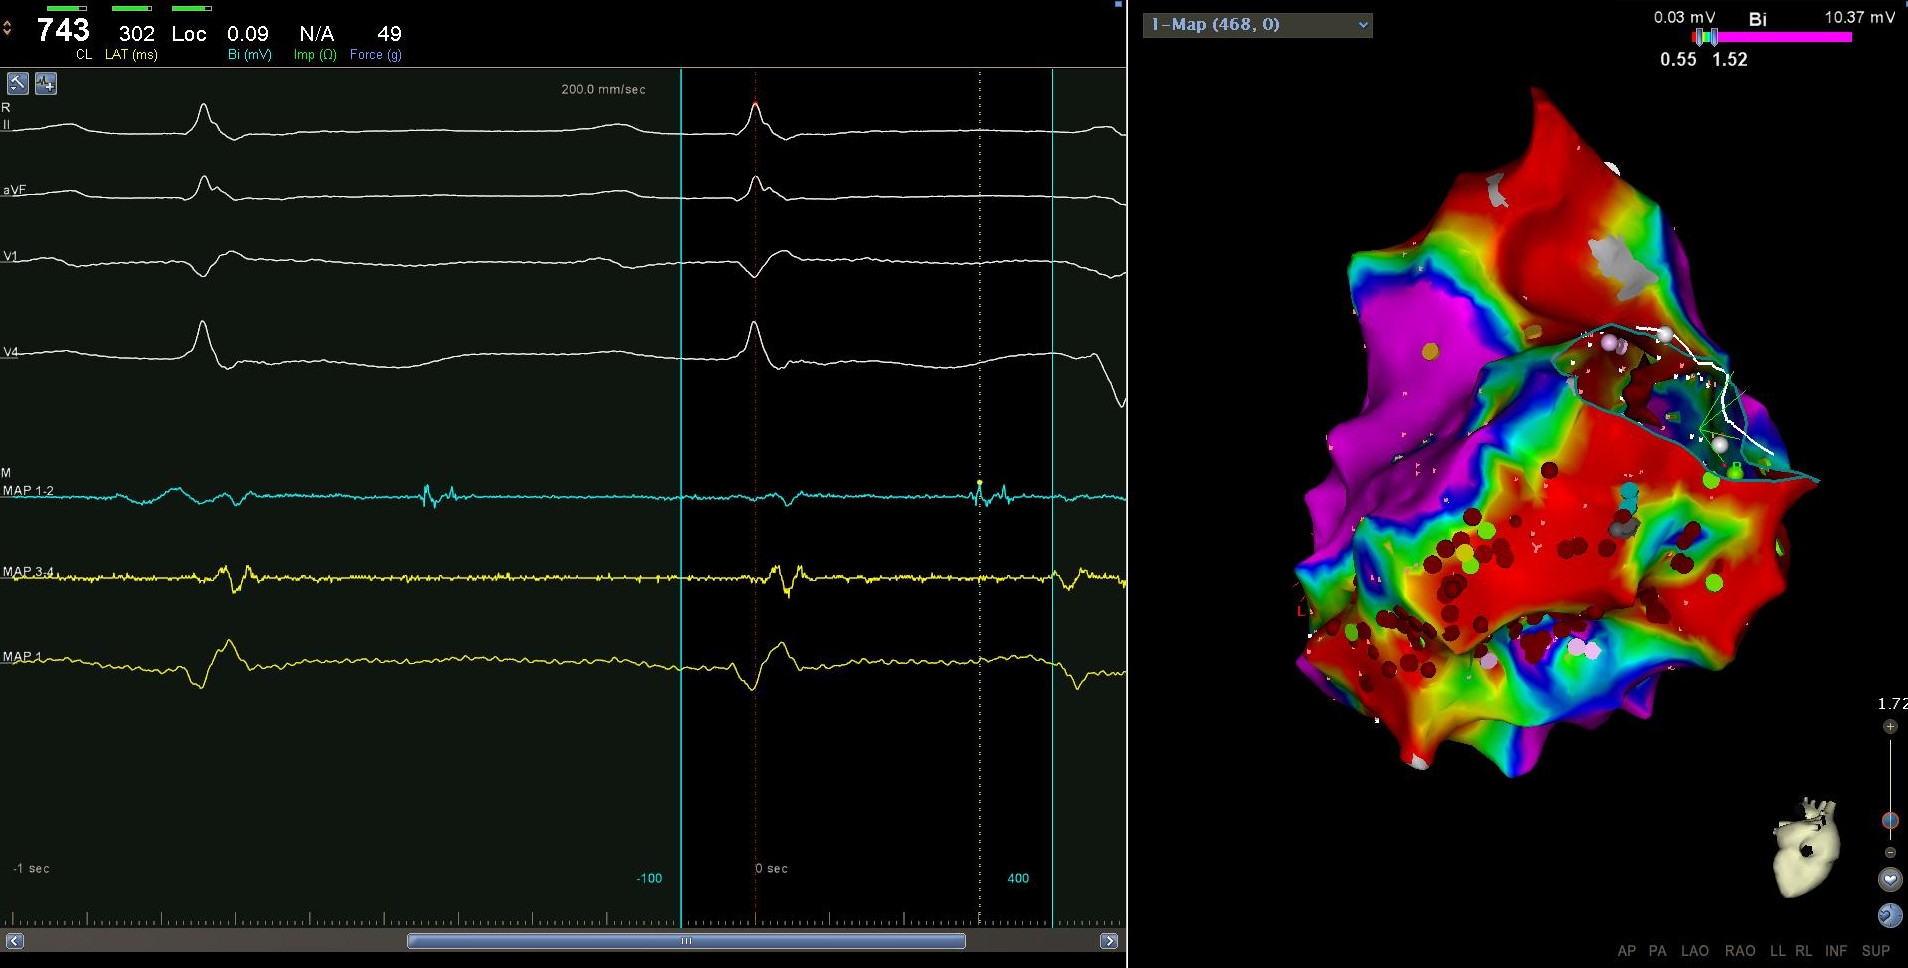

Substrate - Late potentials

ldp_display.jpg

Setting window for substrate mapping

very_late_pot.jpg